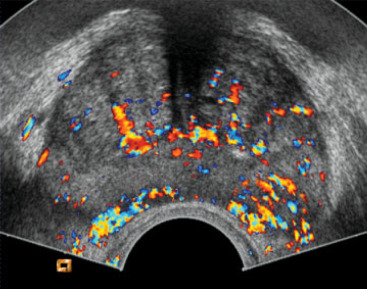

Another major advance in ultrasound is the use of microbubble contrast agents to visualize blood flow and perfusion in the prostate. Tumors typically induce abnormal microvascular patterns – they often have increased blood flow and chaotic vessel architecture due to angiogenesis. Conventional Doppler ultrasound is not very sensitive to slow flow in small vessels, but microbubble contrast can overcome that limitation by enhancing the ultrasound signal from blood.

In CEUS, a contrast agent consisting of microscopic gas-filled bubbles (encased in a lipid or protein shell) is injected intravenously. These microbubbles circulate and reflect ultrasound strongly, allowing real-time visualization of blood perfusion in tissues. In the prostate, a malignant tumor will often demonstrate enhanced contrast uptake (appearing as a focal area of rapid contrast wash-in and wash-out) compared to normal tissue. By observing the contrast kinetics (usually over a few minutes after injection), one can generate Time-Intensity Curves (TIC) for regions of interest. Parameters like Time to Peak (TTP) enhancement, Peak Intensity, Wash-in rate, and Area Under Curve can be quantified. Tumors tend to show a shorter time-to-peak and higher peak intensity (reflecting quicker and greater filling due to neovascularity). For instance, a study by Zhu et al. found that higher grade prostate cancers had a significantly shorter contrast arrival time and time-to-peak, as well as a higher peak intensity than lower grade tissue. This makes intuitive sense: aggressive cancers have more leaky, high-flow vessels that light up earlier on contrast.

CEUS of the prostate is typically performed transrectally simultaneously with B-mode imaging. The microbubbles remain within the vasculature (they do not leak into interstitium), so what is seen is essentially a map of blood volume and flow in the prostate. A cancer might stand out as an “early and bright” enhancing focus. Some cancers, however, especially small or less angiogenic ones, might not show a big difference. Also, inflammation can cause increased blood flow and mimic tumor on CEUS. Nonetheless, multiple studies have shown CEUS-targeted biopsy improves cancer detection. As mentioned earlier, adding CEUS guidance to systematic biopsy increased cancer detection rates by a few percent in some trials. Mitterberger et al. (one of the early pioneers of prostate CEUS) reported that contrast-targeted biopsies could detect ~10% more cancers after an initial negative biopsy round. A 2017 meta-analysis found that CEUS-targeted biopsy had a higher detection rate for clinically significant cancer than systematic biopsy alone, though results varied by study. In absolute terms, sensitivity of CEUS in detecting prostate cancer lesions is around 59–81% with specificity ~70–88%according to a systematic review of parametric ultrasounds. These numbers indicate a notable improvement over unenhanced ultrasound, though not as high as MRI. CEUS particularly shines in identifying hypervascular tumors in the peripheral zone. In the transition zone, BPH nodules can also enhance, which may reduce specificity (one analysis noted CEUS sensitivity ~58% and specificity 70% in peripheral zone, versus 38% sensitivity, 79% specificity in the transition zone).